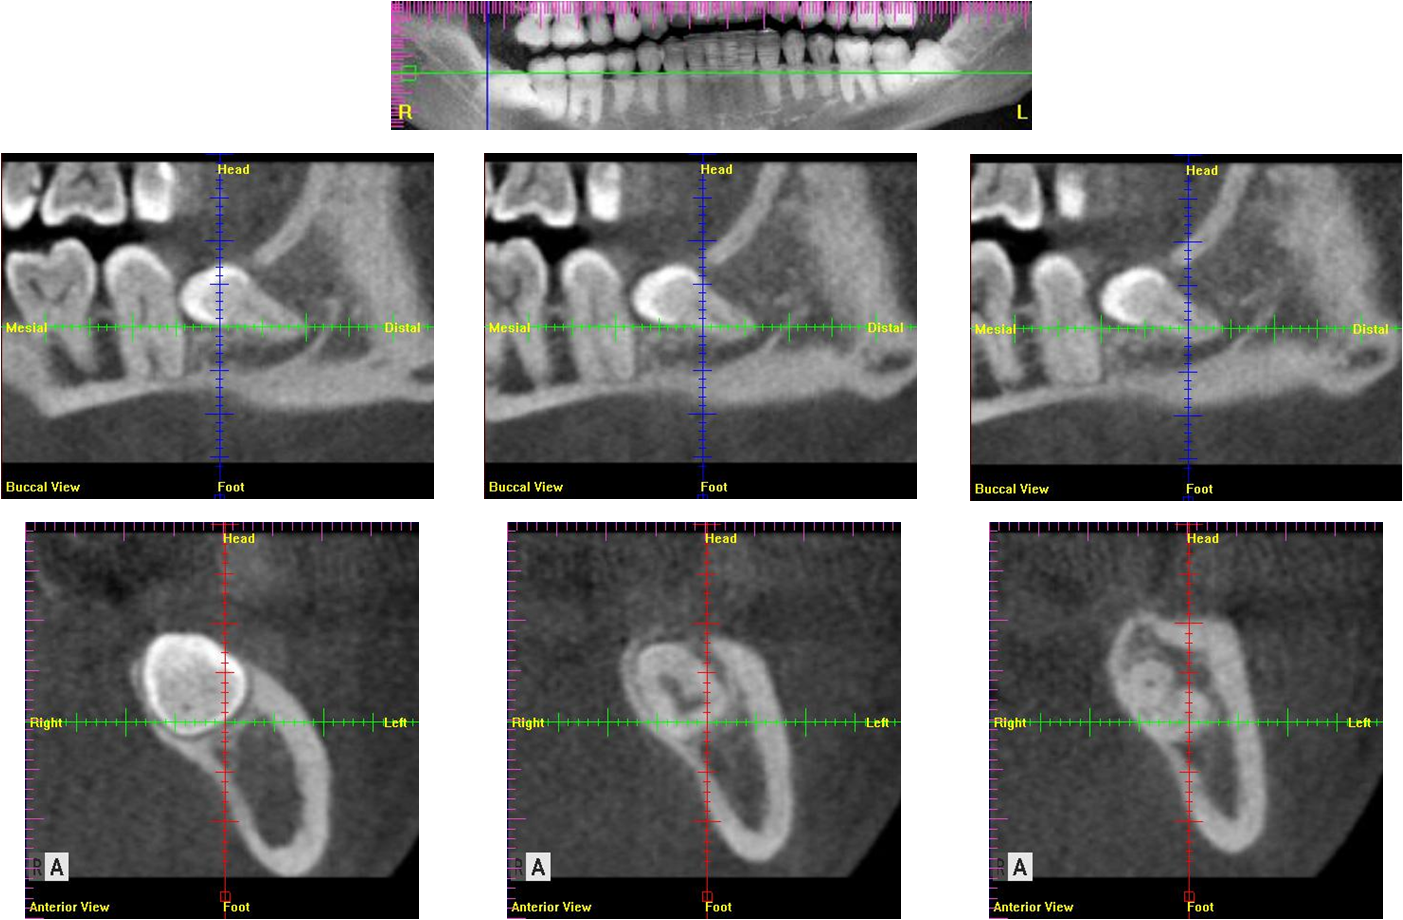

以電腦斷層檢查牙齒位,與鄰近神經